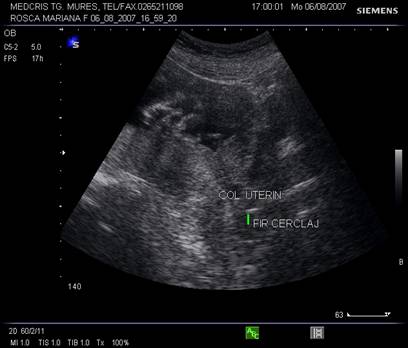

Implicatii terapeutice: urmarirea ecografica a colului uterin decide cerclajul colului uterin; dupa Heath [2], scurtarea colului uterin sub 1,5 cm la 23 saptamani, urmata de cerclaj a scazut semnificativ riscul de nasteri premature.

Fig. nr. 236.